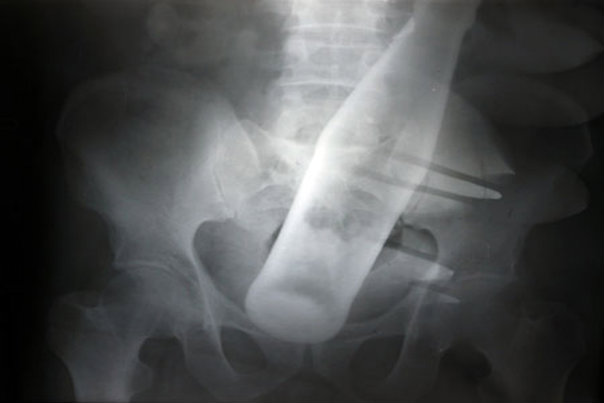

5. Ova snimka boce u trbuhu nepoznatog muškarca dolazi iz bolnice Nishtar u Pakistanu.